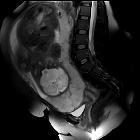

MRI

MRI is the gold standard imaging modality for the placenta and its relationship to the cervix, although in most instances it is not required. Sagittal images best demonstrate the relationship of the placenta to the internal cervical os.